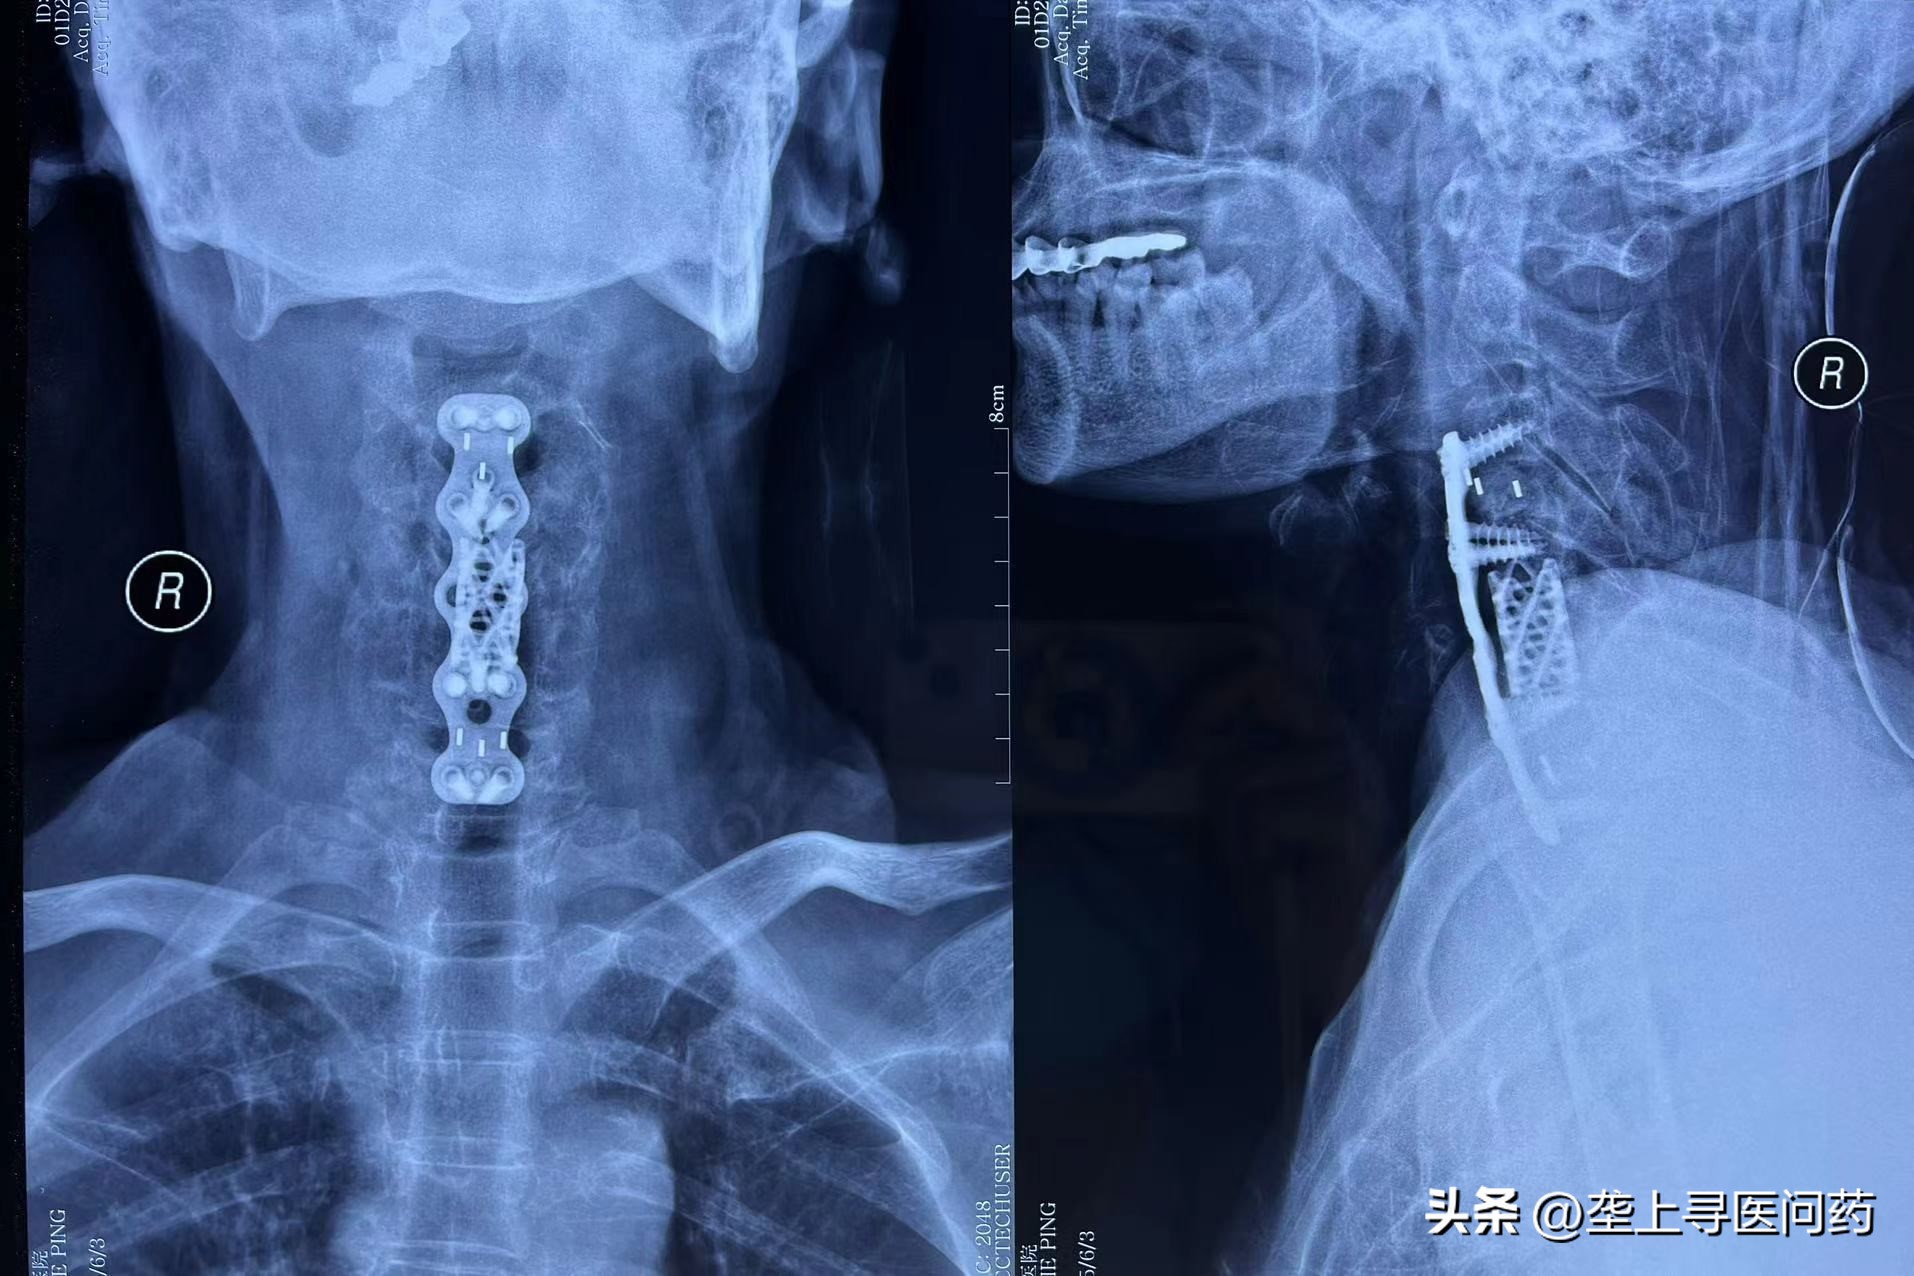

家住硚口的章阿姨去年不慎从楼梯跌落,造成颈椎骨折、颈部脊髓损伤,在外院进行手术后,神志清楚、病情稳定了,但脖子以下不能动弹。但想到今后都只能躺在床上,成为废人一个,66岁的章阿姨觉得天都要塌下来了。

神经康复科主任戴伟通过询问病情发现,脊髓损伤导致章阿姨四肢运动、感觉功能障碍,其翻身坐起、穿脱衣物、二便自理、饮食洗漱等日常生活完全不能自理。同时脊髓损伤导致的周身束缚感,常让章阿姨半夜痛醒,苦不堪言。

尽早康复,解除患者的痛苦,迫在眉睫。完善相关检查后,戴伟主任立刻组织科室医疗、护理技术骨干召开疑难病例专题讨论会,听取病情汇报,根据相关检查和体征结果,对章阿姨进行全面的康复评估,并量身制定了阶段性的康复计划和个性化的诊疗方案。